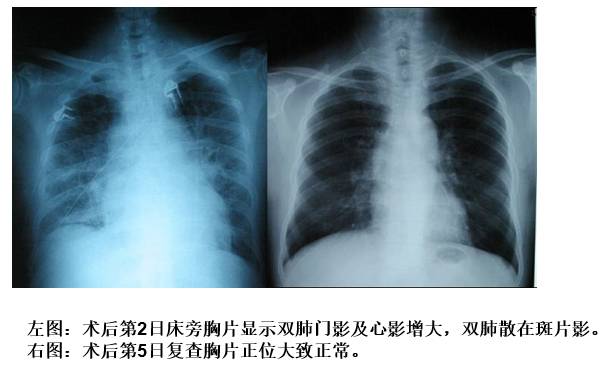

CASE

◆男性,57岁 ,阵发房颤1年余

◆2型糖尿病

◆超声心动图(ECHO)示心房大小正常范围,左室射血分数 60%

◆消融术后第2日夜间患者突发胸闷、憋气、强迫端坐位,咳嗽,咯白色泡沫痰

◆NT-proBNP 由术前155pg/ml升至776pg/ml;

◆动脉血气分析:pH 7.45, pO2:50.6mmHg, pCO2:29.7mmHg;